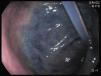

A 44-year-old man residing in a nursing home was receiving enteral nutrition through percutaneous endoscopic gastrostomy (PEG) after suffering an embolism 2 years earlier. He accidentally pulled out his feeding tube. In order to prevent closure of the gastrostomy, a Foley catheter was immediately put in place. Several hours later the patient presented with vomiting. The next day, after the administration of methylene blue through the catheter, the patient underwent an endoscopy, which revealed that the Foley catheter had passed into the pyloric antrum (fig. 1), with the balloon migrating into the duodenum (fig. 2), causing partial obstruction (fig. 3).

The catheter was removed, a 20F Bard® PEG tube was inserted, and the obstruction was resolved. In cases of accidental PEG tube extraction, Foley catheters are frequently used to prevent gastrostomy closure because they are easily passed through the gastrostomy and they are available at the majority of health facilities. However, they do not have an external bumper and peristalsis can pull the balloon into the duodenum, causing gastric outlet obstruction. Rather than having Foley catheter insertion, patients should be rapidly referred to a hospital center within the first 24h so that a PEG tube can be adequately placed. If early referral is impossible, the Foley balloon should be minimally inflated to prevent migration into the duodenum and gastric outlet obstruction (figs. 1–3).